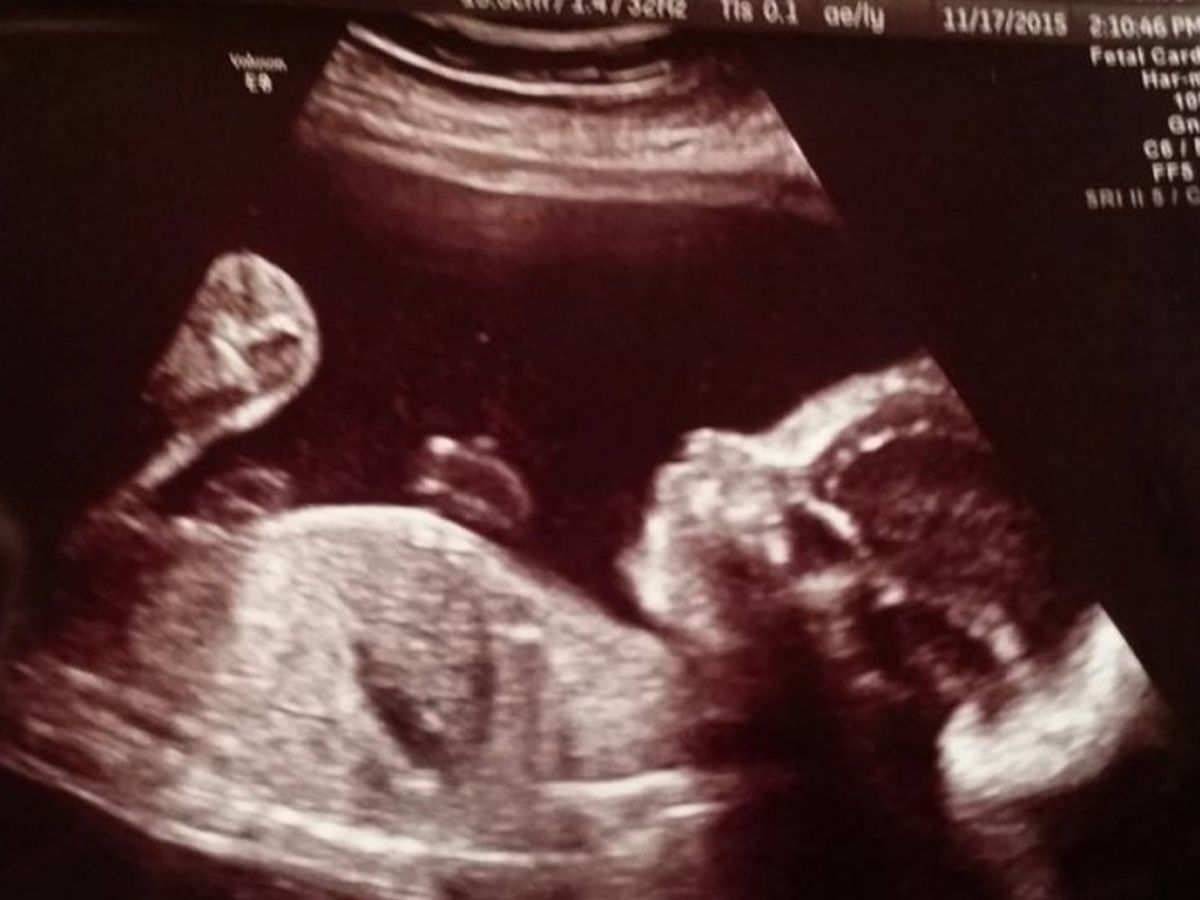

Main fundraiser photo

At 20 weeks Cody and Bryttany went in to Dawson creek hospital for their first ultrasound and were told that they found a small bump on the right side of there baby girl. They were told it was called a cistic hydroma and needed to send the paper work off to children's hospital. That very next day children hospital contacted both Bryttany and Cody. Telling them they needed to meet for an ultrasound.  After children's hospital did their ultrasound they said that it was actually a rare case that they only see every 1- 3 years. It's called a cervical teratoma. The hospital gave them 3 weeks to relocate to Vancouver and live by the hospital to monitor baby. So they both had to leave their jobs and move from Fort St John to Vancouver.

It started out with visits every 2 weeks but the bump started to grow a bit faster and started growing into baby Chacye's neck so now they are doing check ups every week to monitor baby.